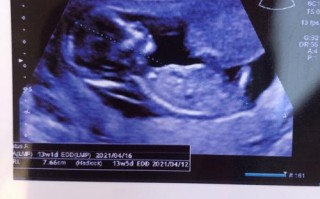

孕期健康知识 孕期13周NT检查是啥? 一句话概括NT检查,全称是颈项透明层厚度检查,是孕早期(通常在11-13周+6天)进行的一项重要的早期唐氏筛查,它通过B超测量胎儿颈后皮肤层的液体厚度,来评估胎儿患有唐氏综合征(21-三体综合征)以及... 99ANYc3cd6 2025-11-28 0 #孕期13周NT检查内容 #NT检查13周注意事项 #13周NT检查结果解读